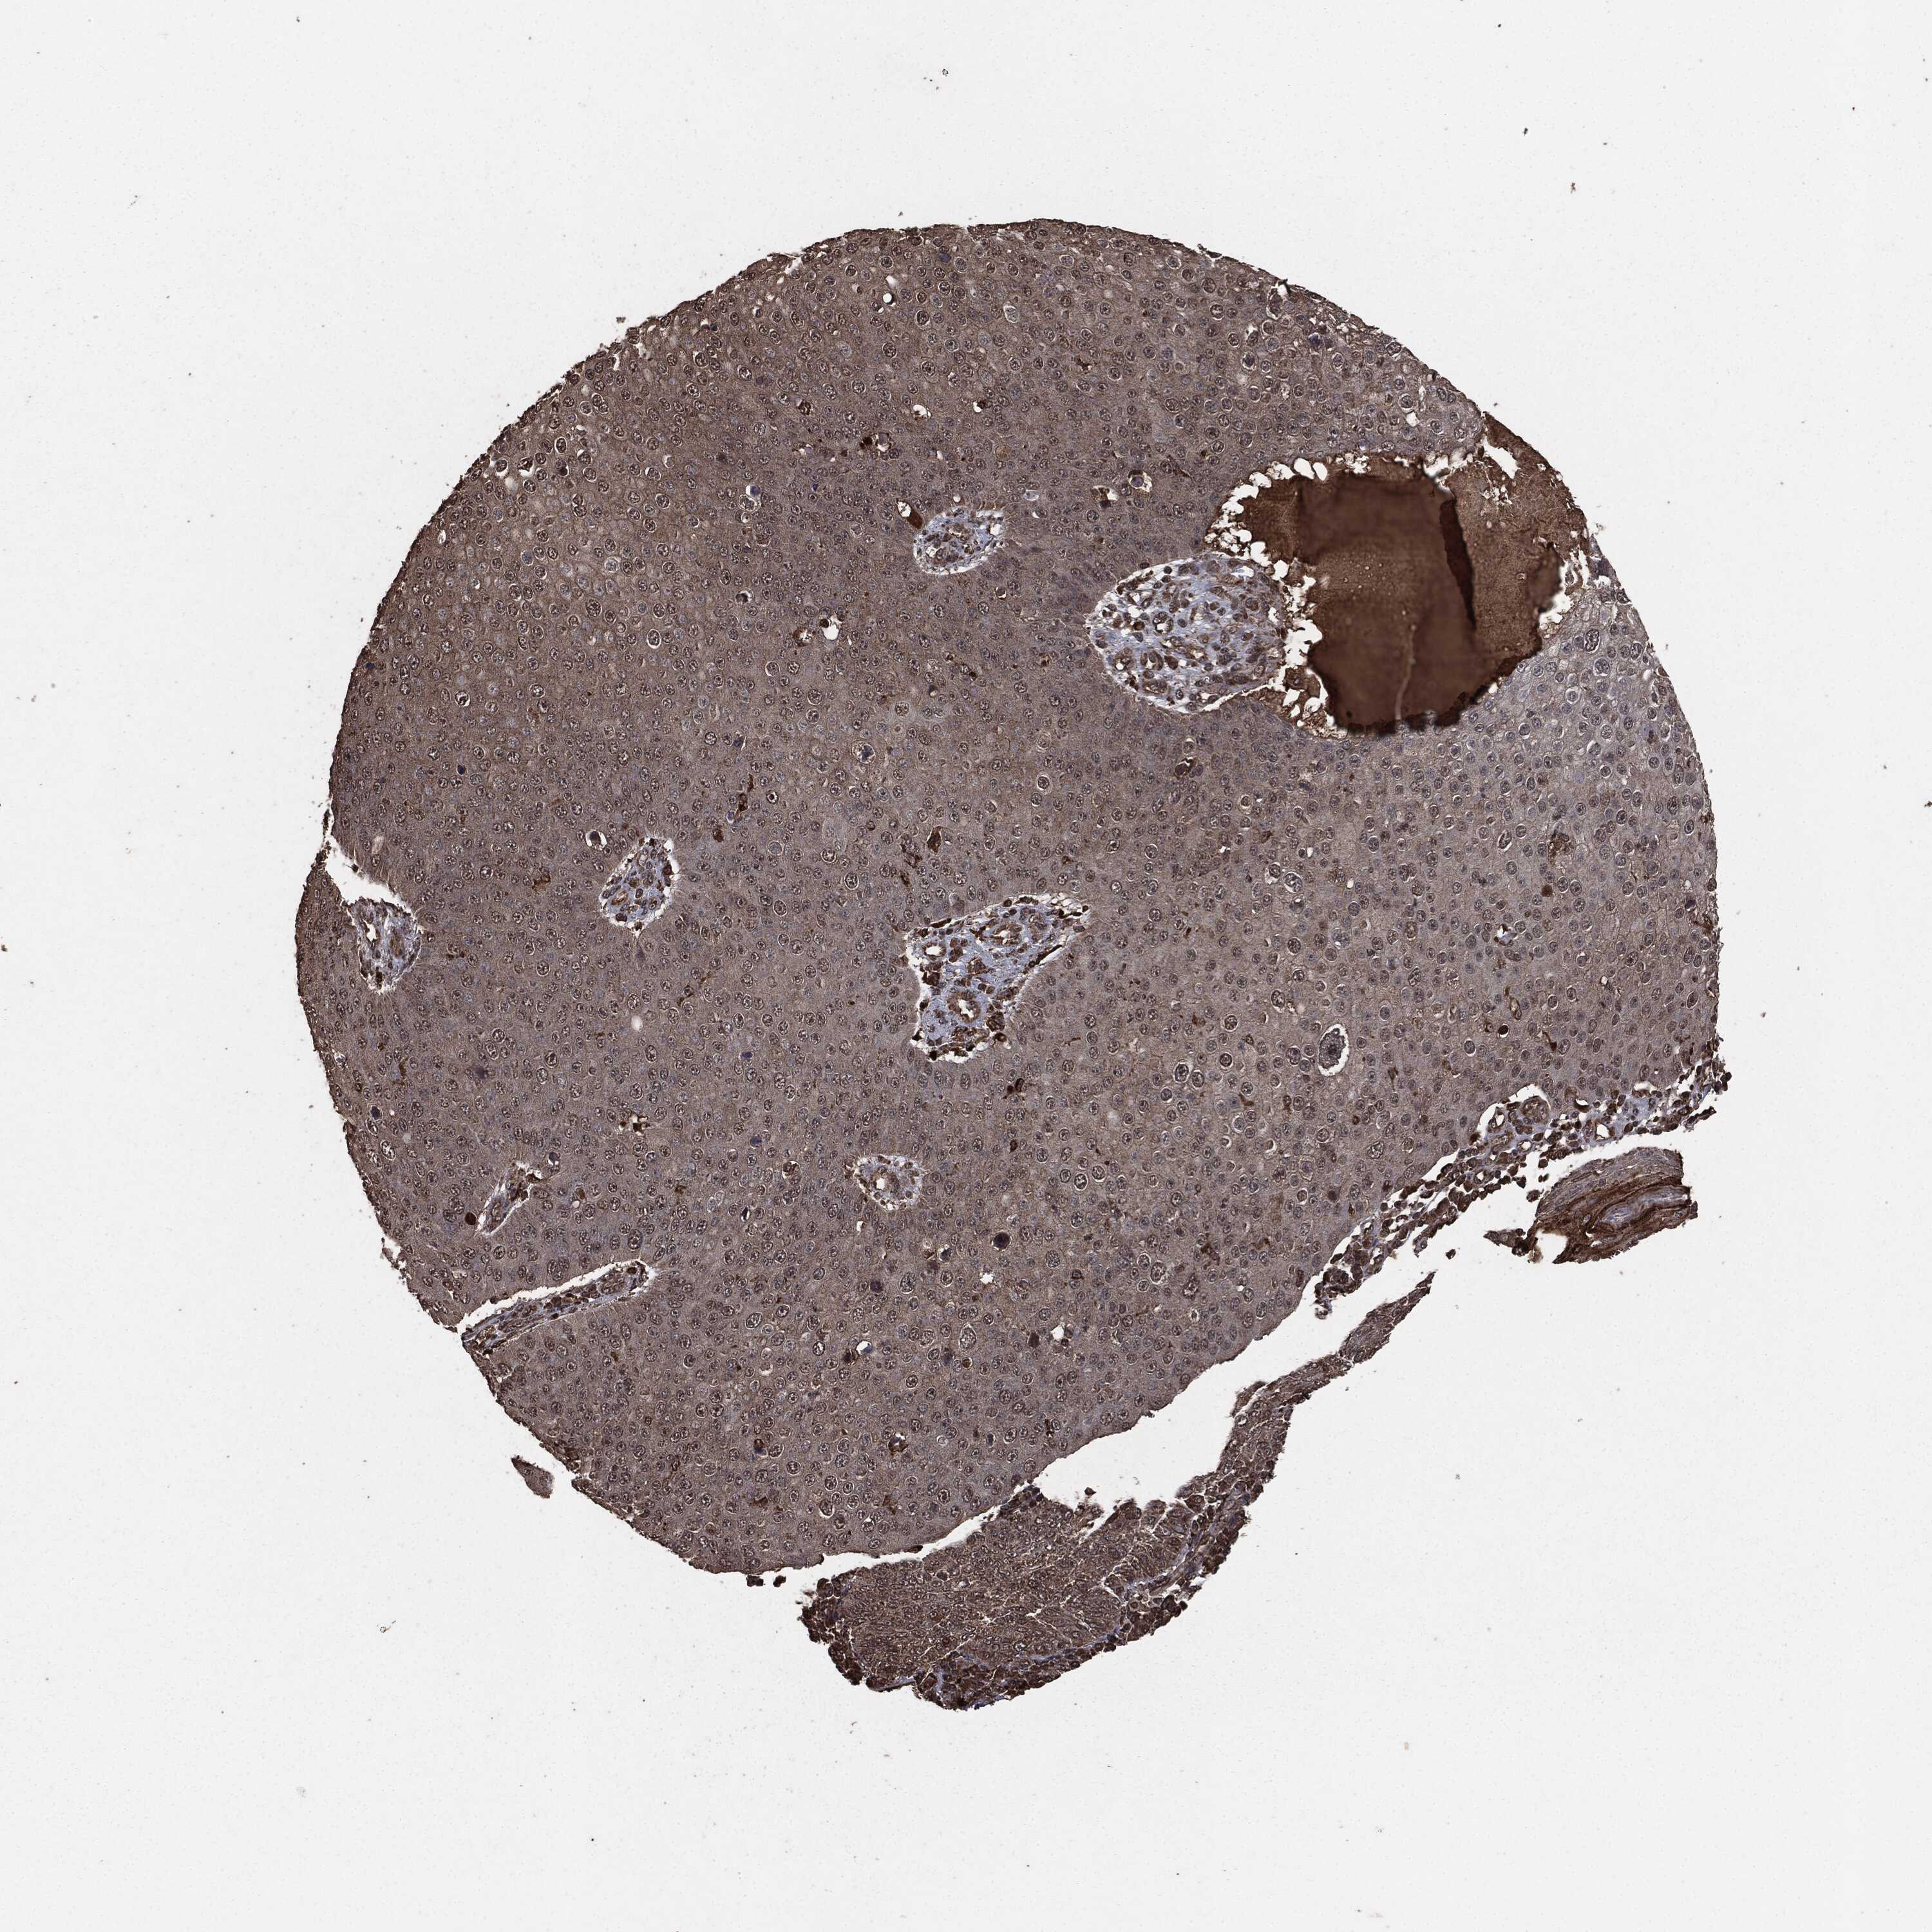

CANCER SKIN CANCER Show tissue menu

SKIN CANCER - Protein expressioni

A mouse-over function shows sample information and annotation data. Click on an image to view it in a full screen mode. Samples can be filtered based on level of antibody staining by selecting one or several of the following categories: high, medium, low and not detected. The assay and annotation is described here.

Each image is clickable and will lead to virtual microscopy that enables deeper exploration of all samples and also displays staining intensity scores, fraction scores and subcellular localization as well as patient and tissue information for each sample.

Basal cell carcinoma